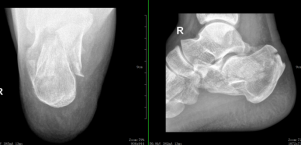

术前照片

术后照片